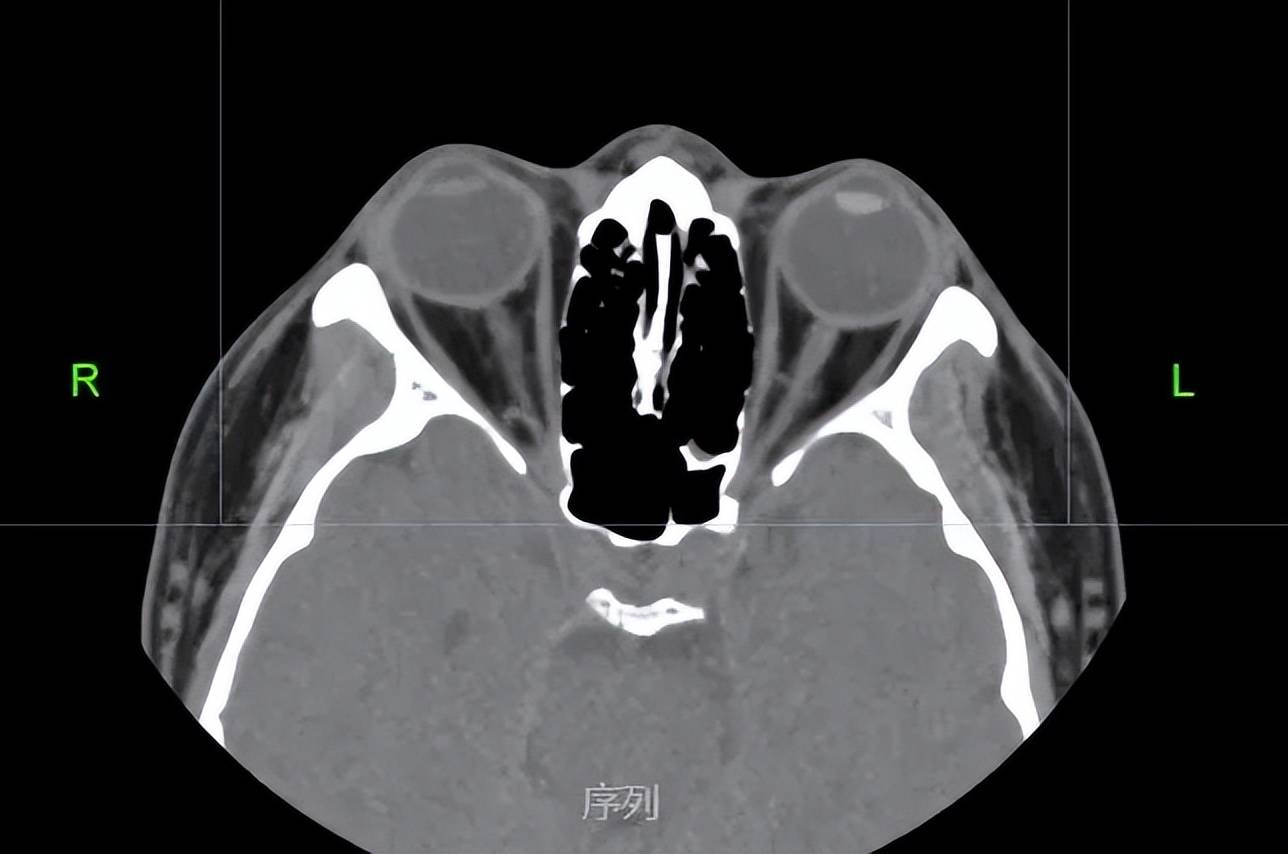

异物打入眼内嵌顿在晶状体上形成外伤性白内障

核性白内障异物打入眼内嵌顿在晶状体上形成外伤性白内障